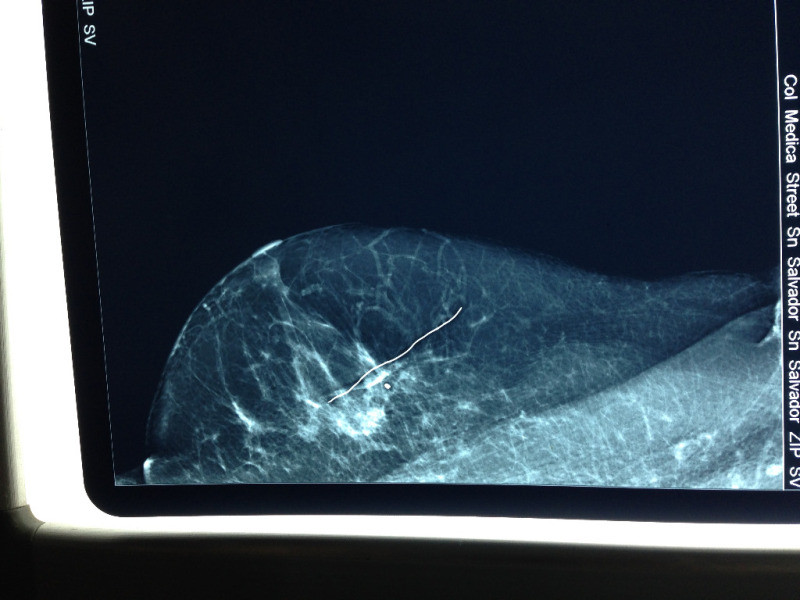

Mamografía de rutina con calcificaciones sospechosas.